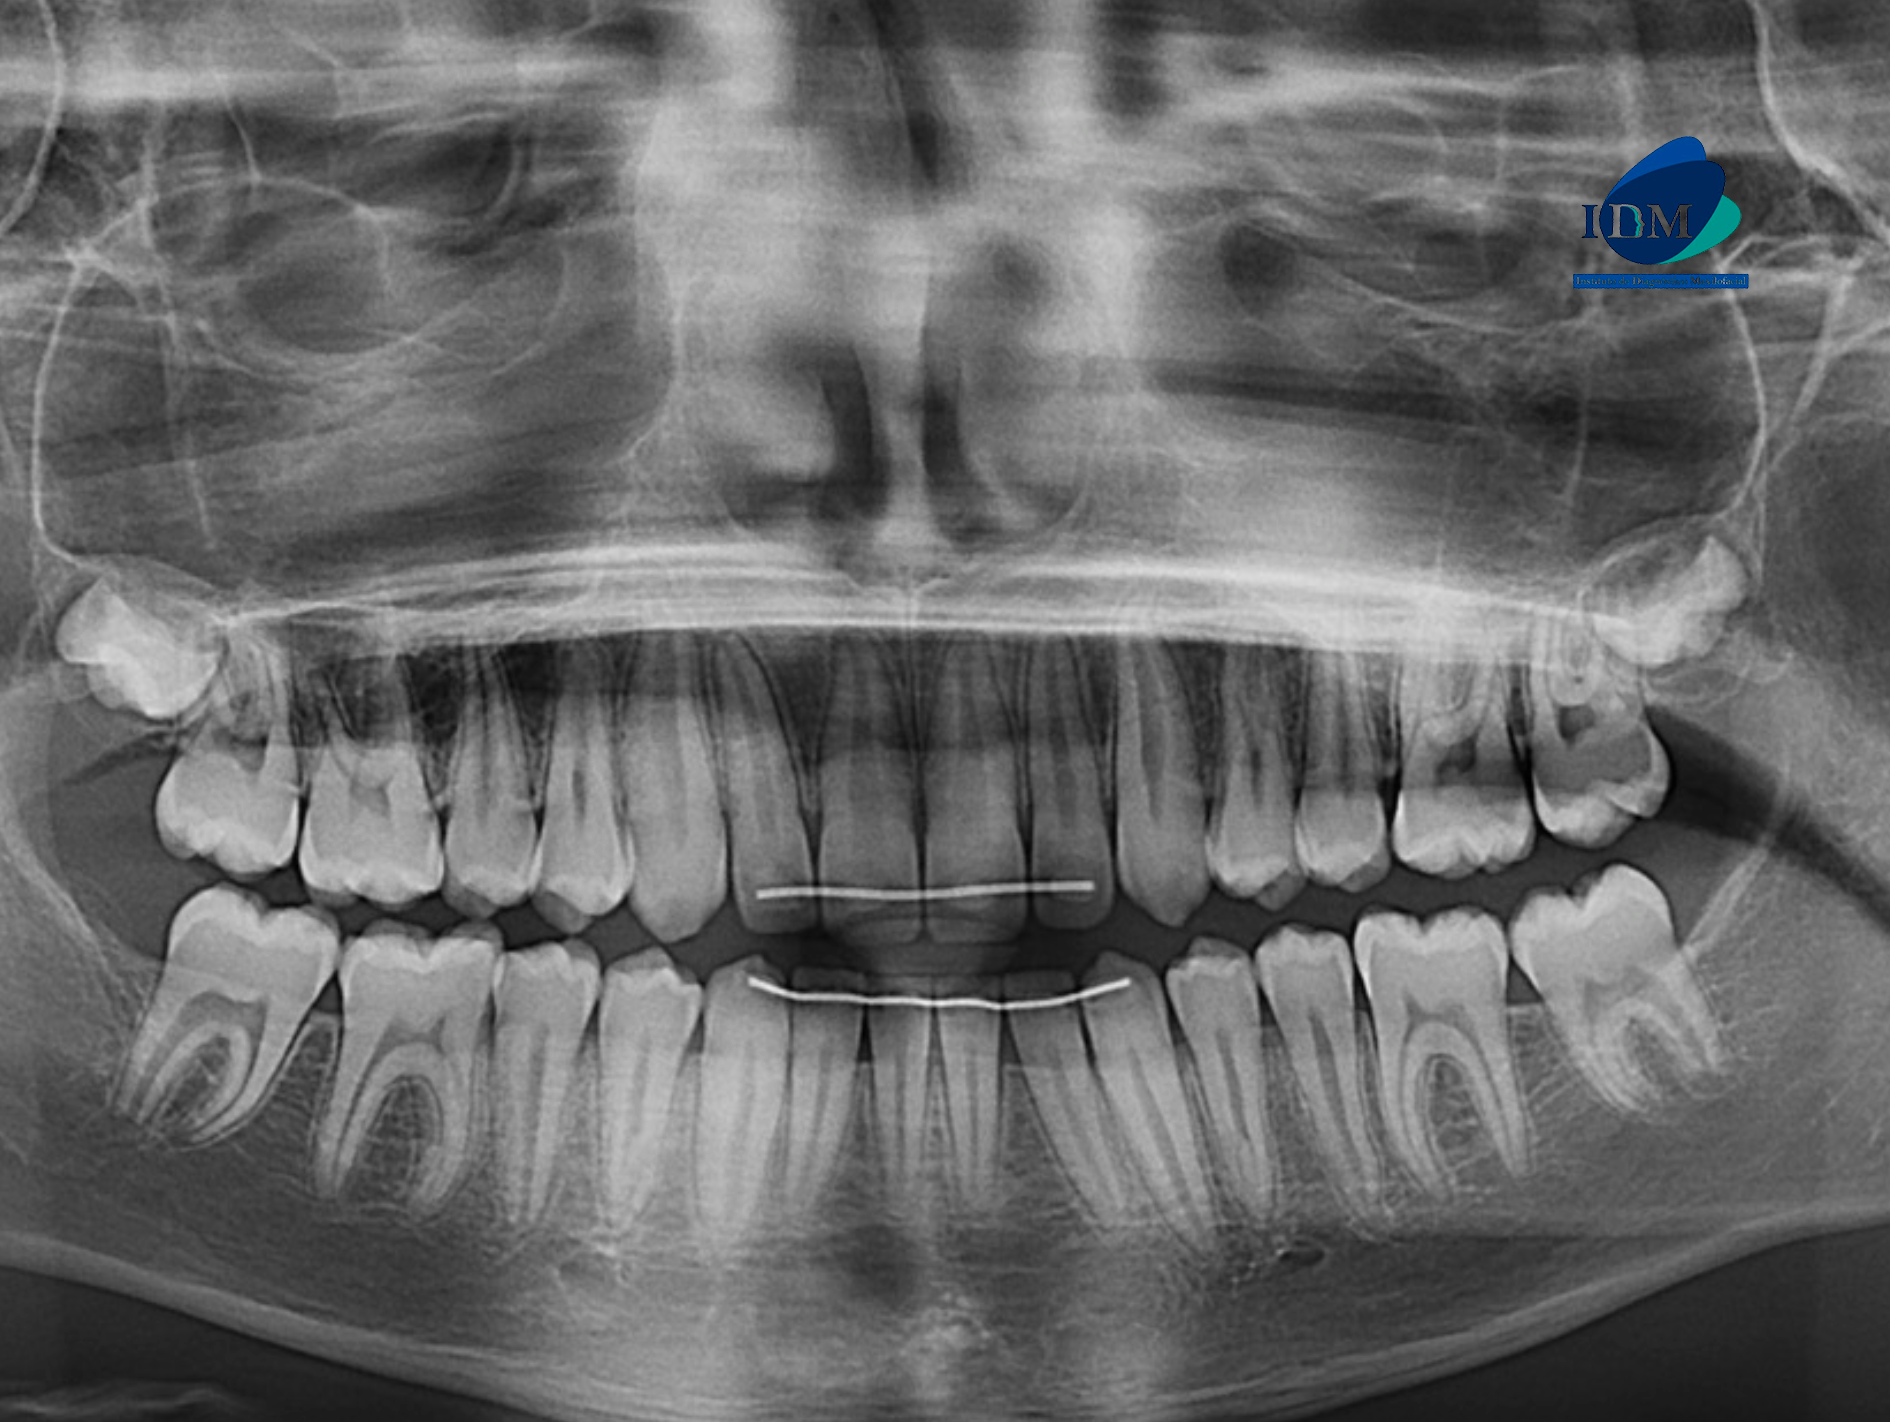

Paciente masculino de 13 años de edad, es referido al Instituto de Diagnóstico Maxilofacial – IDM para evaluación general.

En la radiografía panorámica (Figura 1), se aprecia bifurcación del conducto dentario inferior a nivel distal de pieza 47.

Radiografia Panorámica